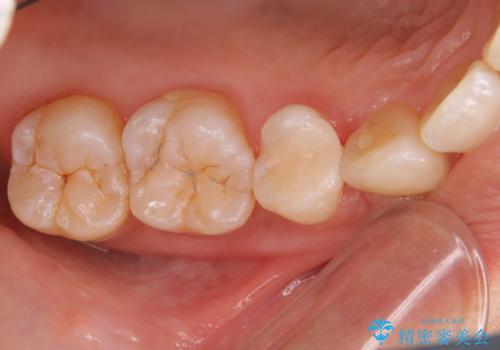

- 銀歯が気になるということで来院された患者様です。

セラミックでの治療を希望されたので治療をいたしました。

銀歯は長い間使用していると隙間ができて、虫歯の原因になります。

そのため適合の良いセラミックをお勧めいたします。